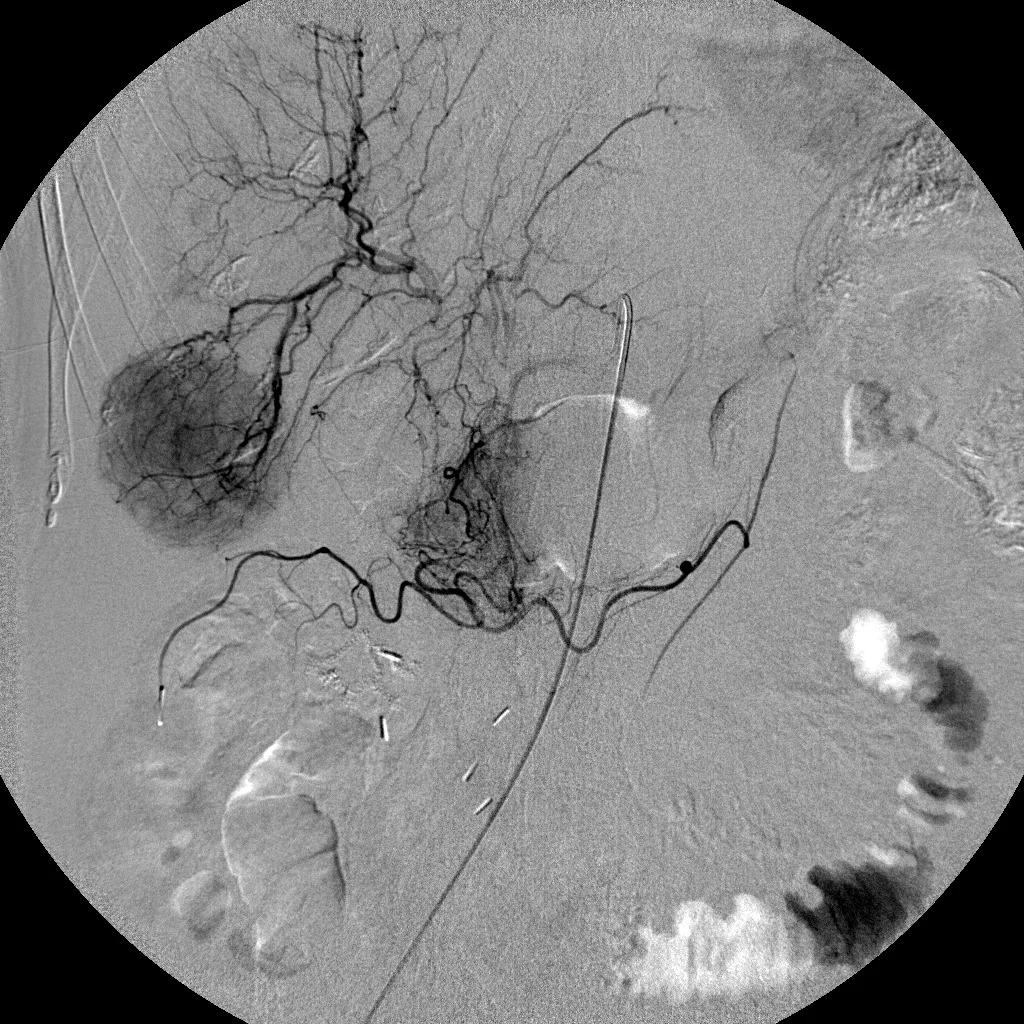

Interventional Oncology: Case 6

61 year old female patient who presented with facial flushing, diarrhea, and multiple liver metastases from carcinoid tumor.